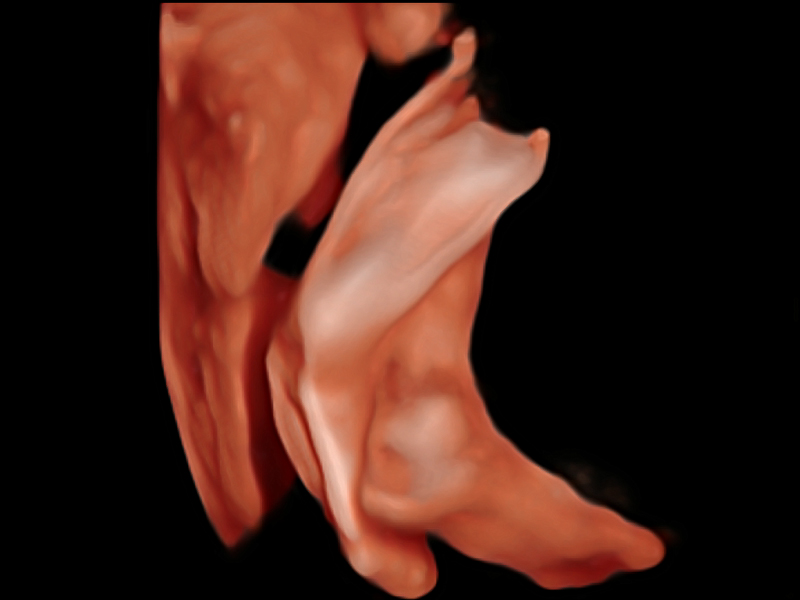

S-Fetus基于大數據深度學習算法,能夠幫助您在產前篩查過程中智能識別胎兒標準切面、自動測量并錄入報告。一個按鍵,即可智能、精準、高效地獲取胎兒生理指標,極大簡化您的產科檢查操作。

可快速對產科掃查切面完成胎兒生理學參數的自動測量,減少操作者按鍵次數,大幅提升檢查效率。